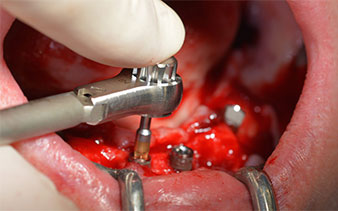

El siguiente ajuste programado es la propia inserción de los implantes. En nuestra clínica, solemos insertar los implantes con una fuerza de 32 Ncm de manera estándar (figs. 12 y 13).

contra-ángulo de W&H

Fig. 12

32 Ncm

Fig. 13

El requisito imprescindible para el tratamiento inmediato es una alta estabilidad primaria. Para satisfacer dicho requisito, en este caso, se prescindió del corte de rosca. La unidad de accionamiento Implantmed de W&H empleada aquí, posee un modo propio para ello que también puede seleccionarse directamente y resulta imprescindible para muchas indicaciones. Los últimos giros para la inserción del implante superaron el valor de 32 Ncm, por lo que se realizaron manualmente. En tales casos, se recomienda utilizar la función autocortante de los implantes y girar el implante varias veces hacia delante y hacia atrás de forma que el implante se aproxime gradualmente hasta su posición definitiva sin ejercer una presión excesiva sobre el hueso (fig. 14).